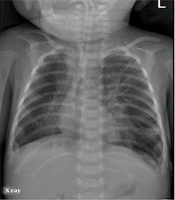

Lung Ultrasonography to Diagnose Bronchopulmonary Dysplasia of Premature Infants

Jing LiuORCID*,

Jing-Han Chi,

Wei Fu,

Li Zhang,

Ru-Xin Qiu